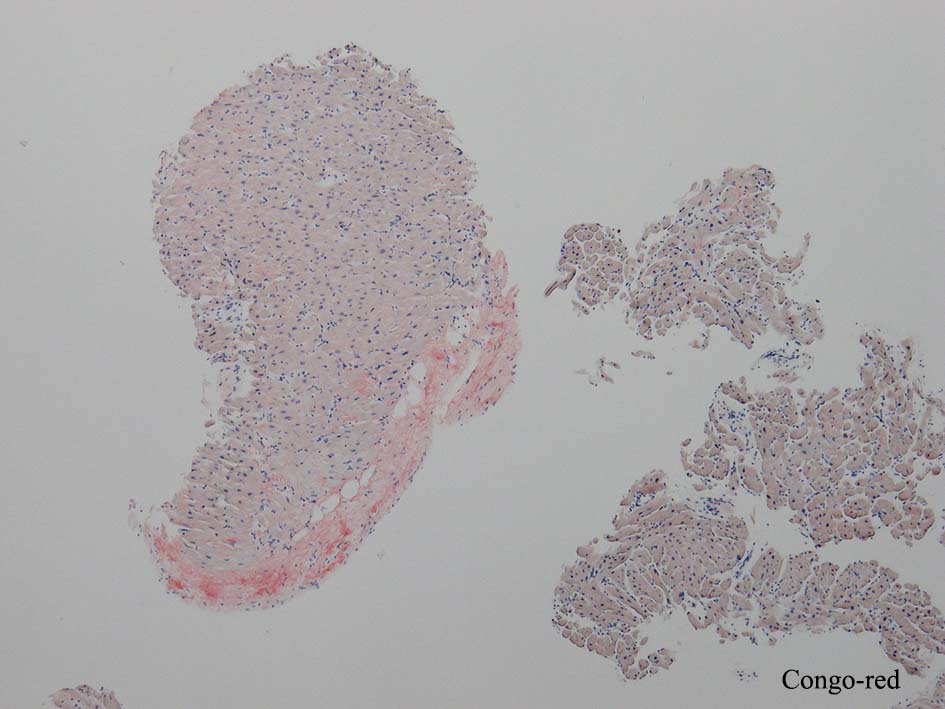

心アミロイドーシス transthyretin type amyloidosis

重症筋無力症/胸腺腫術後で脳神経内科に通院している。平成XX年11月 胸腺腫術後から胸部圧迫感を自覚、半年-1年程前から坂道や階段で息切れが出現し始めた。

4年後の2月 精査目的に当科紹介、精査の結果、心アミロイドーシスが疑われ、確定診断目的で心筋生検が施行される。